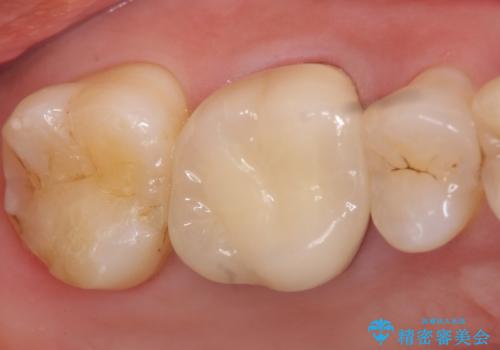

メタルボンドクラウン ゴールドから白い歯へ

金属フレームを用いたメタルボンドクラウンは、オールセラミッククラウンに比べ審美性で劣るというイメージが強いです。しかし歯肉の下までしっかりと被せれば、唇・頬側からは金属部が見えず、十分に審美的です。

また適合もよく、強度も高いので、奥歯の補綴には適したクラウンです。